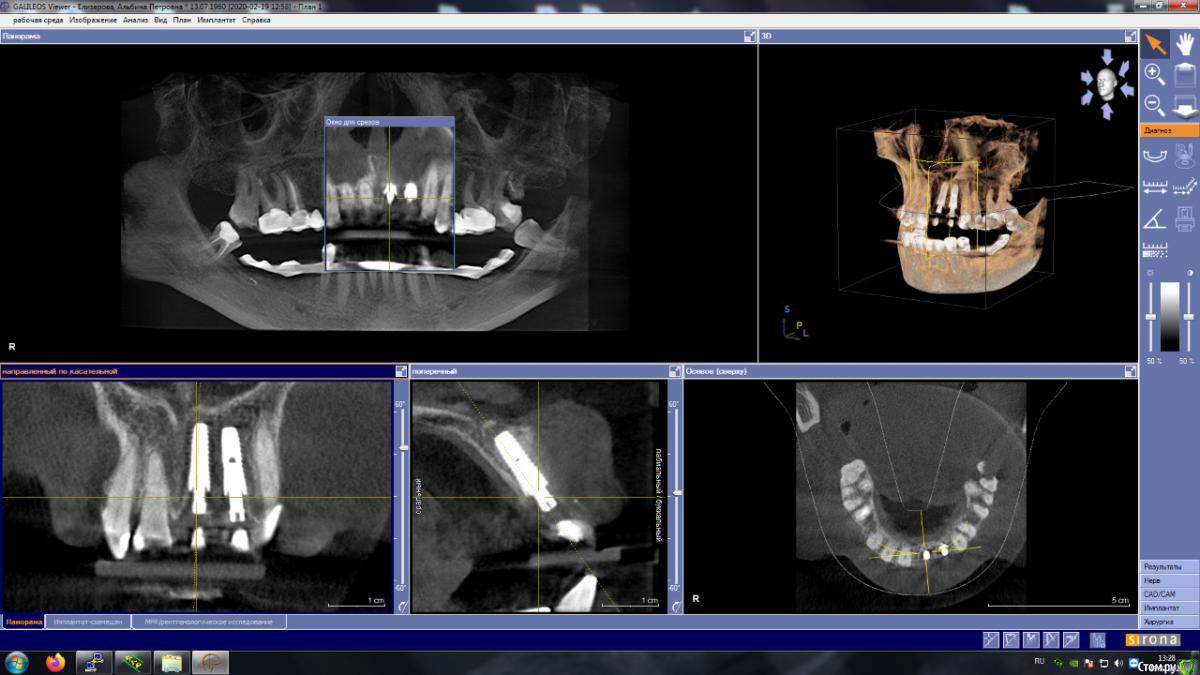

жулля Опубликовано 19 февраля, 2020 Автор Поделиться Опубликовано 19 февраля, 2020 (изменено) Сегодня ходила к другому имплантологу, сделали кт, что скажите Изменено 19 февраля, 2020 пользователем жулля Ссылка на комментарий

Irouil Опубликовано 19 февраля, 2020 Поделиться Опубликовано 19 февраля, 2020 Нужны фото во рту и больше срезов, особенно в области шейки имплантатов, если есть у Вас весь снимок попробуйте выложить его. Судя по тому, что предоставленно, болевые ощущения связаны с давлением края имплантата на десну. Если имплантат выступает не сильно, то это поправимо пересадкой десневого трансплантата над этим местом. И ещё не совсем ясно:И понять шатается имплант или нет, не могу, так коронки качающиеся изначальноКоронки Вам же зафиксировали, они до сих пор подвижны? Ссылка на комментарий

жулля Опубликовано 19 февраля, 2020 Автор Поделиться Опубликовано 19 февраля, 2020 Коронки подвижны опять, и доктор сказал, что мешают коронки, видимо пластмасса не подходит мне. И сказал, что надо ставить постоянные коронки из циркония. Ссылка на комментарий